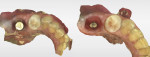

A 5 mm x 10 mm implant (MIS® V3, MIS Implants, mis-implants.com) had been placed at the mandibular first molar site and was ready for restoration. At the uncovering, a custom healing abutment that had been fabricated using an emergence profile management system (Cervico System™, VP Innovato Holdings Ltd, vpicervico.com) to match the emergence profile of a mandibular molar was inserted into the integrated implant, and the soft tissue was sutured around the abutment (Figure 8). After several weeks to allow the soft tissue to heal, the restoration phase began. The custom healing abutment was removed, revealing healthy soft tissue with an emergence cross-section that was relatively square, mimicking a molar (Figure 9).

To avoid potential soft tissue collapse when the impression was captured, a custom impression abutment was created to support the soft tissue and properly communicate to the laboratory technician what had developed intraorally (Figure 10). This technique may be used with either open-tray or closed-tray impression abutments. The impression was taken and the custom healing abutment was reinserted intraorally while the laboratory constructed the restoration. The completed restoration was returned, the custom healing abutment was removed, and the implant restoration was inserted. The result was an emergence profile that mimicked a natural molar, enabling natural-looking esthetics (Figure 11). A radiograph demonstrated a smooth transition emanating from the implant platform to support an emergence profile that allowed soft-tissue maintenance and helped to eliminate potential food traps (Figure 12).